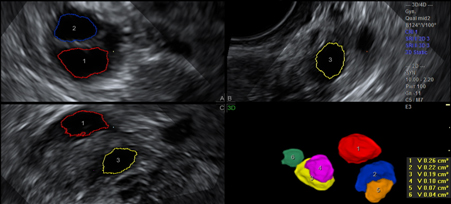

卵泡三维超声监测卵巢窦卵泡数量,评估卵巢储备功能

子宫输卵管超声造影(hysterosalpingo-eontrastsonography,HyCosy)是在超声监视下,通过向宫腔注入各种阴性或阳性造影剂,实时观察造影剂通过宫腔、输卵管时的流动及进入盆腔后的分布情况,以判断输卵管通畅性,同时还能观察子宫、卵巢及盆腔情况。Hycosy所用造影剂一般分为两类:一类为阴性造影剂,如生理盐水。另一类为阳性造影剂,如过氧化氢、Echovist(一种由半乳糖制成的,能产生回声的微气泡造影剂)等。影响HyCosy检查结果准确性的因素除造影剂外,超声仪的分辨率也十分关键。二维超声图像上较难区分输卵管情况。然而三维超声可克服上述缺点。多项研究己经证实,HyCosy作为近年来一项新兴技术,在评价输卵管通畅性方面与HSG的准确性相似,同时在超声引导下还能综合评价盆腔脏器情况,特别是在观察子宫肌层组织、附件及卵泡成熟度上具有HSG无法比拟的优势,且无X线对人体的损害等特点,目前正逐步成为不孕症的一线检查手段。